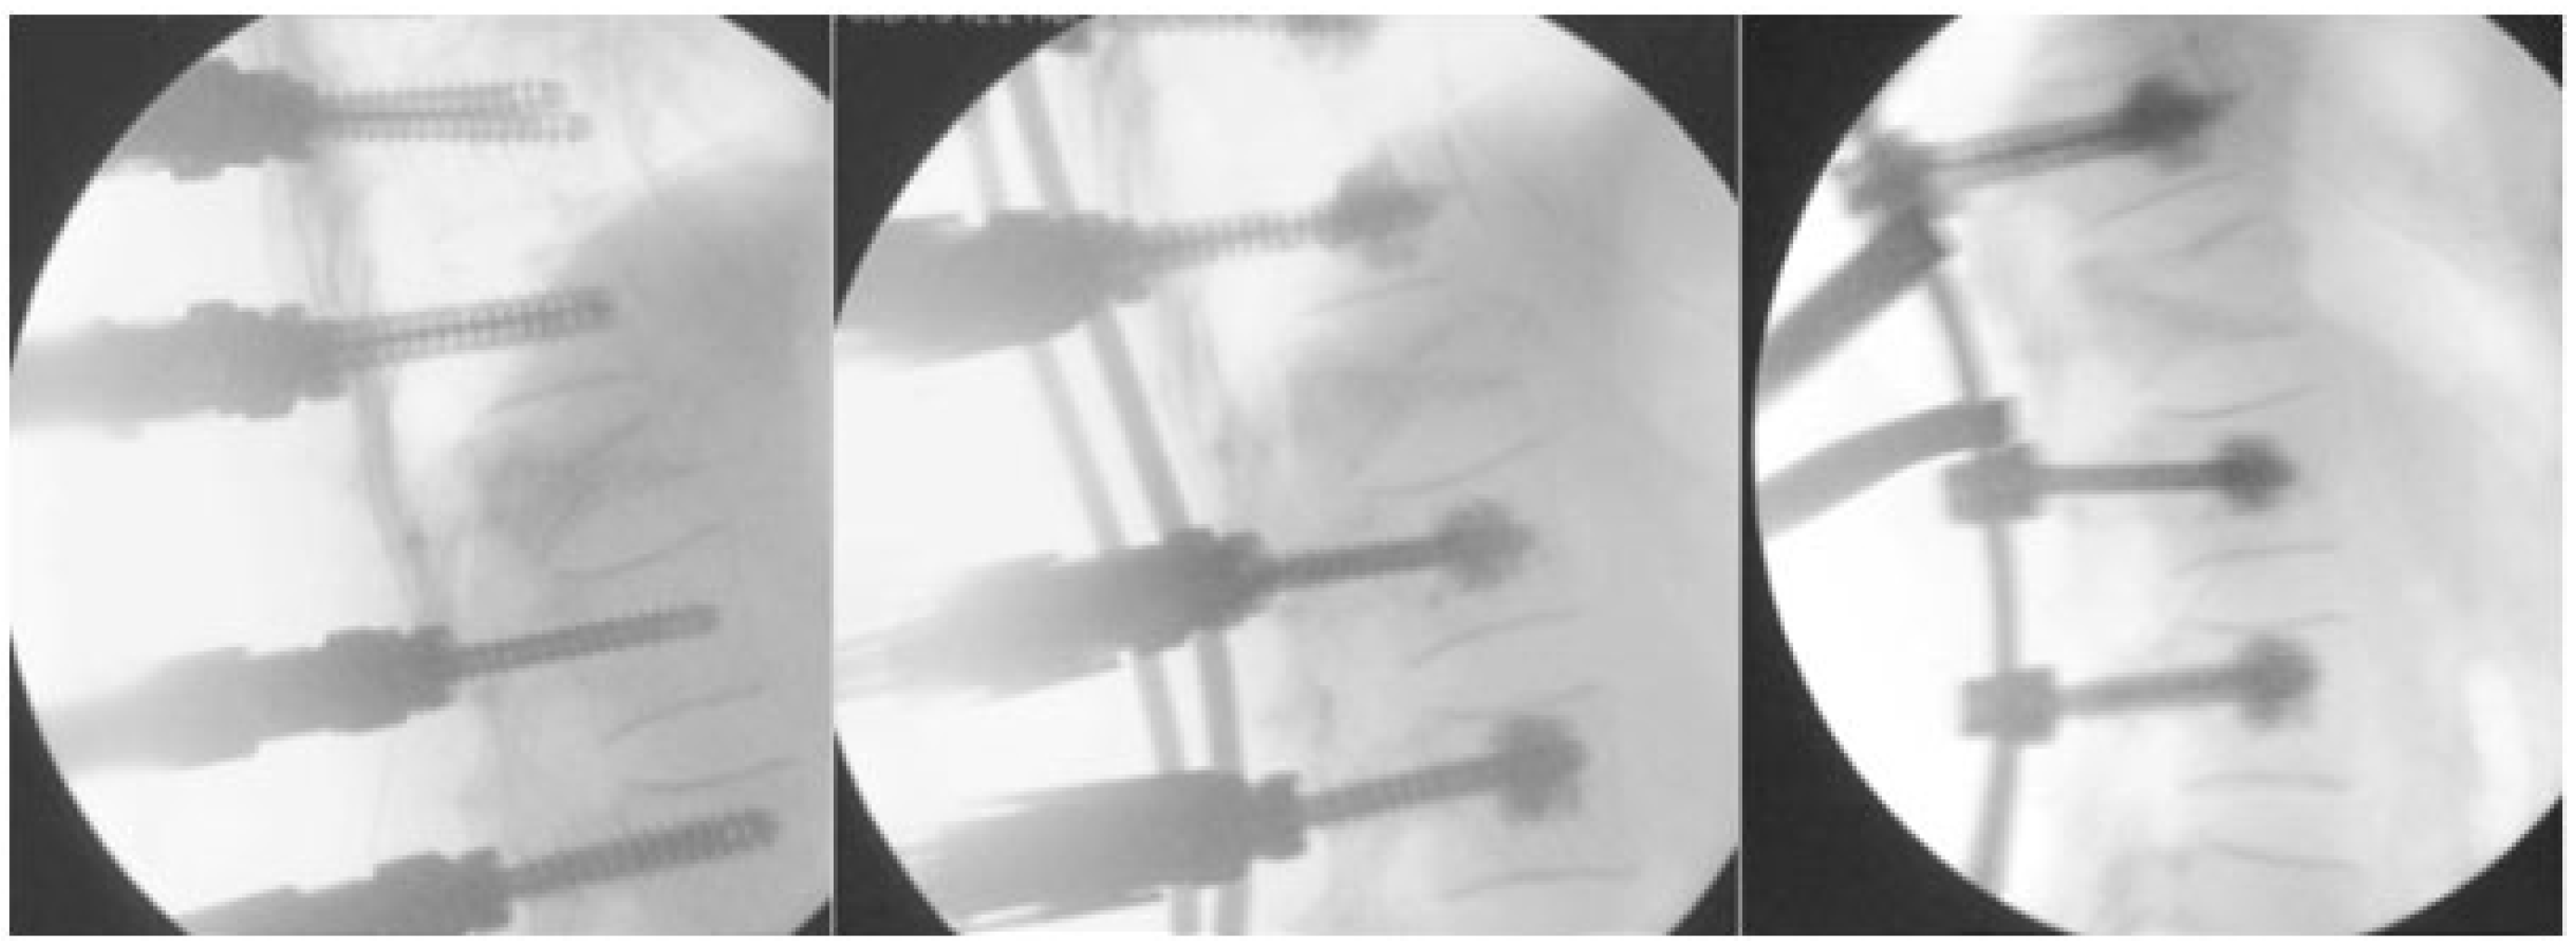

- Unrestricted reconstruction of datasets with views along the path of the needle with planning in 3D and 2D reconstructions (Figure 1).

- Decreased X-ray exposure for the MISS technique. Navigation enables a reduction in X-ray exposure to the surgical team and the patient. Through a real time visualization of instruments, skin incisions and trajectories can be planned [21].